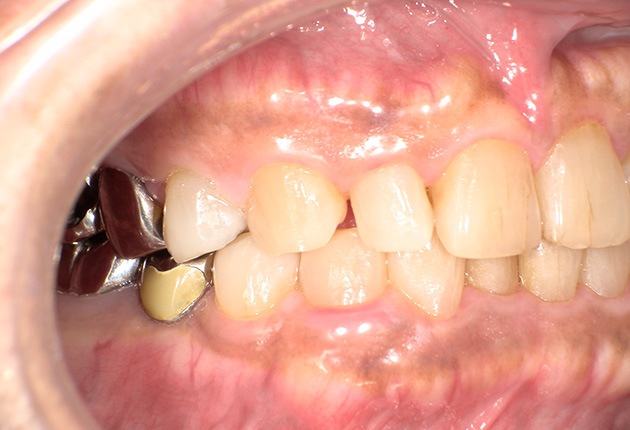

90分の治療で銀歯の状態からキレイな状態になります。噛み合わせの調整や審美面も使用しながら合わせます。

良く噛めて安心と、ご満足いただき大変嬉しく思います。笑顔も一層素敵になりました。

| 治療内容 | 欠損部インプラント 不正咬合に対し不良補綴のやり直しと合わせて咬合再構築 |